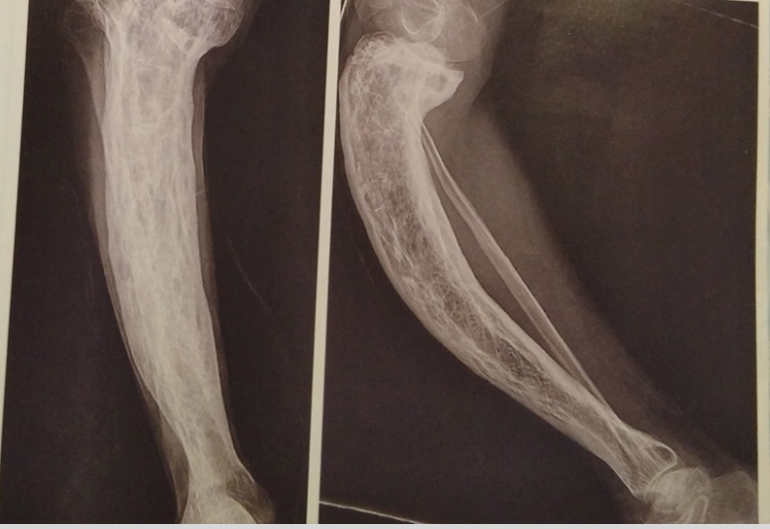

التغيرات المرضية في المفصل نتيجة الروماتيزم

في مرض الروماتيزم (التهاب المفاصل الروماتويدي)، يُصاب الغشاء الزليلي الذي يبطّن المفصل بالتهاب مزمن، مما يؤدي إلى تضخّمه وزيادة إنتاج السائل الزليلي، فينتج عن ذلك تورم في المفصل وألم وتيبّس في الحركة، خاصة في الصباح. ومع استمرار الالتهاب، تبدأ الخلايا المناعية في مهاجمة مكونات المفصل، مما يؤدي إلى تآكل الغضروف والعظم المجاور، وقد يتسبب ذلك بمرور الوقت في تشوّه المفصل وفقدان وظيفته.